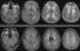

CADASIL or CADASIL syndrome, involving cerebral autosomal dominant arteriopathy with subcortical infarcts and leukoencephalopathy, is the most common form of hereditary stroke disorder, and is thought to be caused by mutations of the Notch 3 gene on chromosome 19. The disease belongs to a family of disorders called the leukodystrophies. [Source: Wikipedia ]